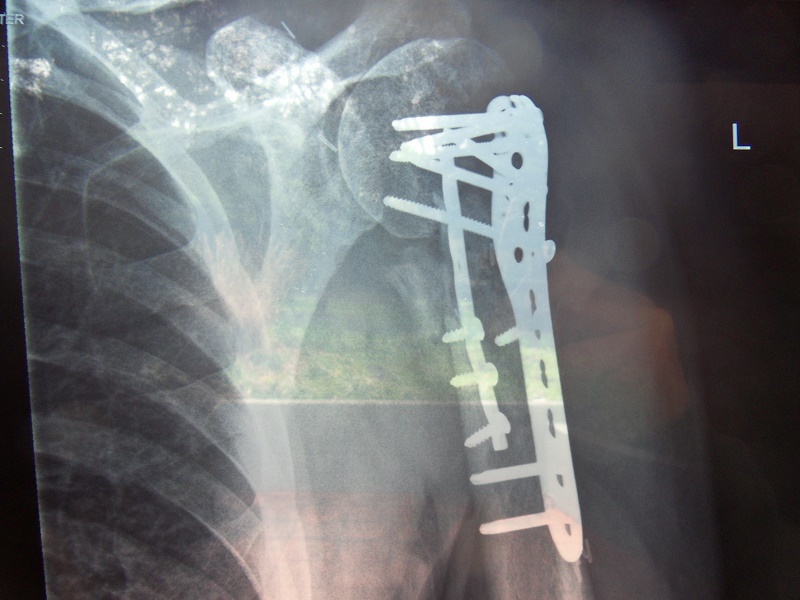

Please see the aftermath of my 9th of August crash on my dirtbike.

The pictures pretty well sum up the story... :roll:

few screws too many....

Shit Pete, thats a mess... I guess all that is saying in there.?

Wow Pete that is a lot of extra hardware in there!

Geepers Pete, that's a lot of hardware :-/